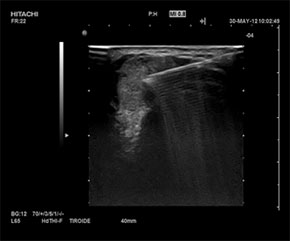

Nodulul tiroidian reprezinta o delimitare distincta a parenchimului tiroidian fata de tesutul vecin, evidentiata clinic vizual sau prin palpare si/sau ecografic. Odata cu utilizarea pe scara larga a ultrasonografiei s-a observat o crestere a prevalentei nodululor tiroidieni clinic nepalpapili (intre 20-76 % din populatia generala).

Evaluarea paraclinica a nodulilor tiroidieni cuprinde: ecografia tiroidiana, testele functionale tiroidiene (primordial este TSH, dar si calcitonina), citologia prin PUNCTIA ASPIRATIVA CU AC FIN (FNA-FINE NEEDLE ASPIRATION), scintigrafia tiroidiana (doar in cazuri selectionate); RMN si CT nu sunt examene de rutina in evaluarea nodululor tiroidieni.

Punctia-aspiratie pe ac fin este indicata in cazul tuturor nodulilor mai mari sau egali cu 10 mm, cu caracteristice ecografice suspecte. Dintre acestea amintim cateva: nodul hipoecogen sau unic, nodul solid, margini neregulate, circulatie intranodulara haotica, microcalcificari, adenopatia patologica.